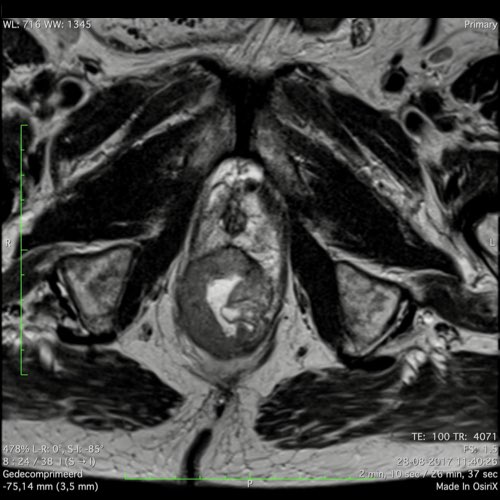

Hình ảnh

Các hình ảnh được cung cấp cho thấy ung thư biểu mô tế bào nhẫn với tình trạng dày lan tỏa thành trực tràng, hình ảnh bia bắn điển hình, và sự xâm lấn mỡ mạc treo trực tràng.